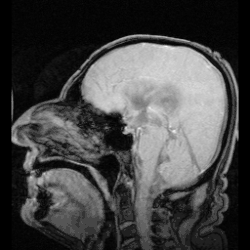

Badania z użyciem tomografii komputerowej komór w późnych latach 70. XX wieku rzuciły nowe światło na wiele zaburzeń psychicznych. Badacze zauważyli, że osoby cierpiące na schizofrenię miały większe komory mózgowe w porównaniu ze średnią badanych grup. Był to pierwszy dowód na biologiczne podstawy schizofrenii, który doprowadził do renesansu badań z wykorzystaniem metod obrazowania. Rezonans magnetyczny (MRI) wyparł z czasem tomografię komputerową jako podstawowe narzędzie w badaniach nad wpływem anomalii układu komorowego na choroby psychiczne.

Wciąż nie jest pewne, czy powiększone komory mózgu są skutkiem, czy przyczyną schizofrenii. Komory mózgu są również powiększone w przypadku demencji, co tłumaczy się często czynnikami środowiskowymi[6]. Należy jednak pamiętać, że w populacji ludzkiej istnieją duże różnice międzyosobnicze w wielkości komór, tak że procentowa różnica w ich wielkości między średnimi u osób zdrowych a chorych na schizofrenię (16%) nie jest bardzo odległa od naturalnych wahań w ich wielkości (zasięg zmienności wielkości komór mózgu u osób zdrowych to 25% do 350% średniej)[7].